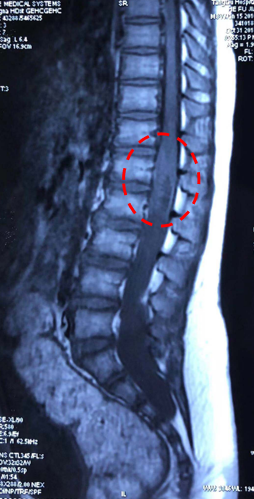

男,8岁大小便失禁伴双下肢肌力下降25天小便失禁为突出症状诊断:骶管囊肿、脊髓圆锥中央管扩张?表皮样囊肿?

本例脊髓圆锥及终丝呈囊性扩张,术中探查未见表皮样囊肿成分

合并骶管囊肿,囊肿内无神经根,囊肿处理关键为封闭硬膜囊漏口,而非单纯填充肌肉或脂肪组织,更非引流。